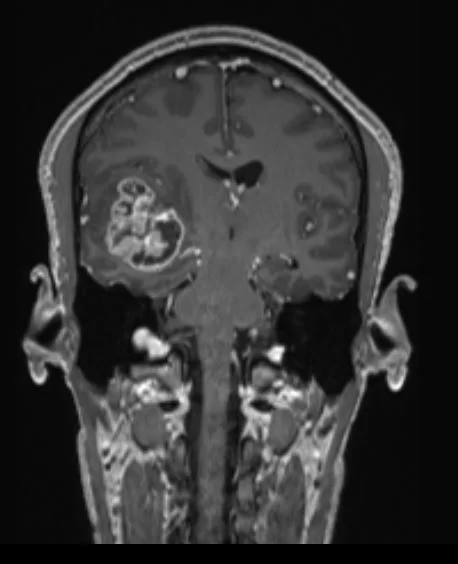

H Μαγνητική Τομογραφία εγκεφάλου ανέδειξε εκτεταμένη χωροκατακτητική εξεργασία δεξιά κροταφικά με πίεση επί του σύστοιχου κροταφικού κέρατος και σημαντικό περιεστιακό οίδημα.

Αρχικά διενεργήθηκε ενδελεχής έλεγχος στα πλαίσια προετοιμασίας της χειρουργικής επέμβασης (οπτικά πεδία: φυσιολογικά), λειτουργική μαγνητική τομογραφία (fMRI) και δεσμιδογραφία).

Προεγχειρητικά ο όγκος και η σχέση του με τις σημαντικές ανατομικές δομές και λειτουργίες μελετήθηκε με τη βοήθεια της λειτουργικής μαγνητικής και της μαγνητικής δεσμιδογραφίας. Με απλά λόγια, αυτές οι εξετάσεις μας έδειξαν πόσο μακριά είναι ο όγκος από όλα εκείνα τα στοιχεία που θέλουμε να προφυλάξουμε.